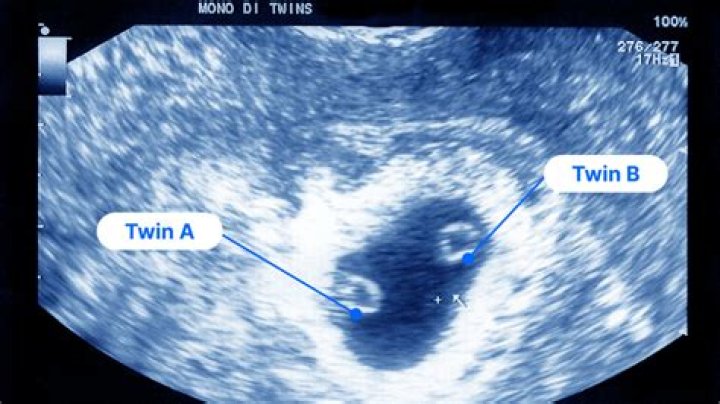

Can you see twins on a 4 week ultrasound?

An ultrasound scan is the only way to confirm that you're pregnant with twins (McAslan Fraser nd, NICE 2011). The earliest you're likely to find out is between 10 weeks and 14 weeks, when you have your dating scan (McAslan Fraser nd, NHS 2019, NICE 2011). Ultrasound is almost foolproof at diagnosing twins.

Can twins be seen at 6 weeks?

It's possible to see twins (or more) on an ultrasound at around six weeks, though one baby may be missed at this early stage. Sometimes a heartbeat is seen in one sac, but not in the other. Rescanning in a week or two may reveal a second heartbeat, or the scan may show that one sac is growing and the other still empty.